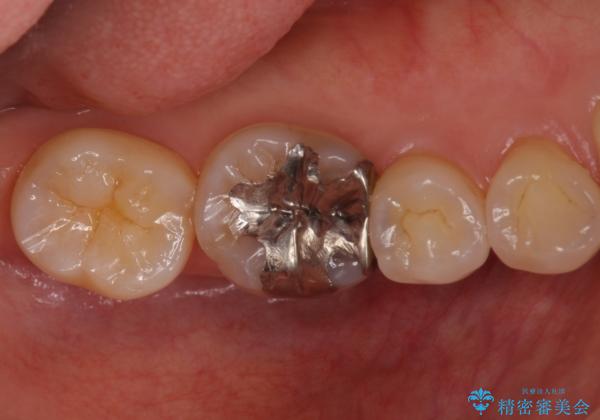

銀歯を白く セラミックインレーに

- 銀歯にしたのが20年以上前とのことで、白くやりかえたいということでした。

セラミックインレーにしています。

- 7万円(左下6 emaxプレスインレー 7万円)費用は治療当時の料金となります

銀歯を外して、下に虫歯があればしっかり取ります。しみるなどの症状が出る前がおすすめです。